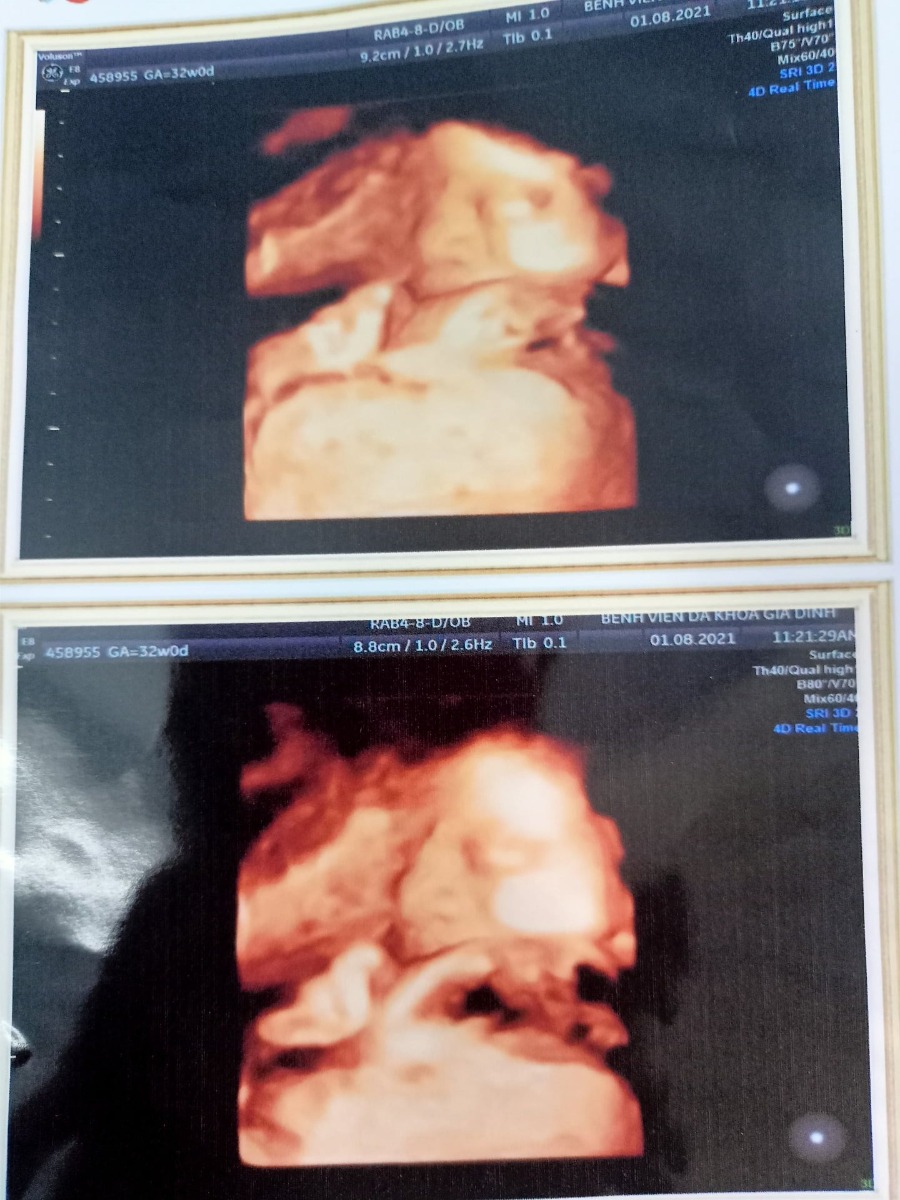

Nay thành phố lockdown mẹ chẳng mua que test được chỉ biết hằng ngày theo dõi con đạp. Mà con lỳ quá cơ ngày thì sơ sơ sương sương tối thì đạp khí thế làm mẹ mất hết cả ngủ 😅😂Mẹ vẫn cố gắng mong con đủ ngày đủ tháng ra chơi với ba mẹ. Đến giờ mẹ vẫn chưa biết mặt con lúc thì lấy chân, tay che mặt, lúc thì nằm úp. lúc thì dây rốn che 😁. Thôi chờ ngày con chào đời mẹ nhìn mặt trực tiếp vậy.